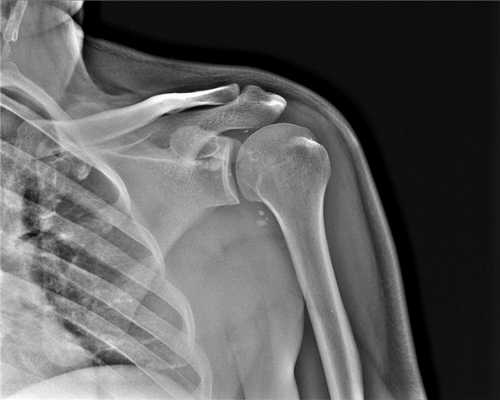

Слева) Передне-задняя рентгенограмма: молодой человек с болью после падения. Ширина акромиально-ключичного сочленения равна 12,4 мм; верхняя границы нормы составляет 6 мм. Клювовидно-ключичное расстояние нормальное, следовательно, это II тип акромиально-ключичного вывиха.

(Справа) Передне-задняя рентгенограмма: пациент с III типом акромиально-ключичного вывиха. Дистальный конец ключицы приподнят относительно акромиона и также имеется расширение между ключицей и клювовидным отростком на >50% по сравнению с нормальной стороной (не показано). (Слева) На передне-задней рентгенограмме у пациента с болью в плечевом суставе после травмы можно видеть потерю конгруэнтности акромиально-ключичного сустава, но без расширения и подъема латерального конца ключицы.

(Справа) Fla аксиллярной рентгенограмме у этого же пациента визуализируется задний вывих ключицы относительно акромиальной суставной поверхности. Это IV тип акромиально-ключичного вывиха. Для вправления ключицы часто требуется оперативное вмешательство.

2. Рентгенография при травме акромиально-ключичного сустава:

• Нормальная рентгенограмма при травме акромиально-ключичного сочленения I типа

• Передне-задняя проекция: увеличенное акромиально-ключичное расстояние при II типе:

о >6 мм

о Измеряют минимальное расстояние

о Пограничные случаи: сравнивают с другим плечевым суставом

о Не разрешают пациенту поддерживать поврежденную руку:

- Поддерживание руки может уменьшить степень смещения

• III тип: приподнятый латеральный конец ключицы:

о У 20% нормальных плечевых суставов латеральный конец ключицы несколько приподнят:

- Может потребоваться рентгенография противоположного плечевого сустава

о Акромиально-ключичный сустав обычно также расширен

о Увеличение клювовидно-ключичного (КК) расстояния:

- Расширение >50% сравнивают с неповрежденной стороной

- 14 мм

о Если клювовидно-ключичное расстояние нормальное, предполагают перелом клювовидного отростка:

- Перелом клювовидного отростка лучше визуализируется в осевой проекции или проекции Stryker notch